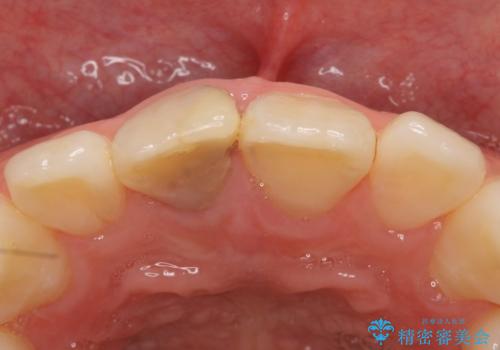

- 右上1番目の前歯の変色が気になるといらっしゃった方の症例です。

再根管治療後、オールセラミッククラウンによる補綴を行いました。

- オールセラミッククラウン…¥100,000、仮歯…¥10,000、ファイバーコア…¥20,000、精密根管治療費別途費用は治療当時の料金となります